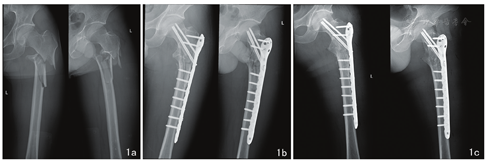

本组45例,男30例,女15例;年龄为25~65岁,平均35.6岁。左侧20例,右侧25例。致伤原因:跌伤7例,交通伤15例,高处坠落伤23例。骨折类型:股骨颈基底部骨折6例(Garden分型:III型2例,IV型4例);股骨粗隆间骨折29例(按Evans’s标准分型:I型4例,II型8例,III型13例,IV型4例);股骨粗隆下骨折10例(图1a)。所有患者均为闭合性骨折。单纯股骨粗隆部骨折患者34例;合并其他骨折患者11例,其中腰椎骨折3例、桡骨远端骨折4例、跟骨骨折4例。本组患者无合并胸腹部外伤。所有患者入院后急诊行胫骨结节骨牵引,其中桡骨远端骨折者予复位石膏托固定,跟骨骨折者予外敷中药。所有患者均于受伤后3~7 d手术。术前Harris评分均<70分。

本组45例,手术时间58~85 min,平均70 min;术中出血量50~200 ml,平均120 ml;住院时间15~21 d,平均17 d。45例均获随访,随访时间6~24个月(平均10个月)。所有患者均骨性愈合,骨折临床愈合时间术后3~11个月,平均5个月。术后复查X线片均复位满意(图1b,图1c),无感染、内固定松动及畸形愈合等并发症。术后6个月根据Harris评分评定患髋功能:优26例,良16例,可3例,差0例,优良率为93.3%。